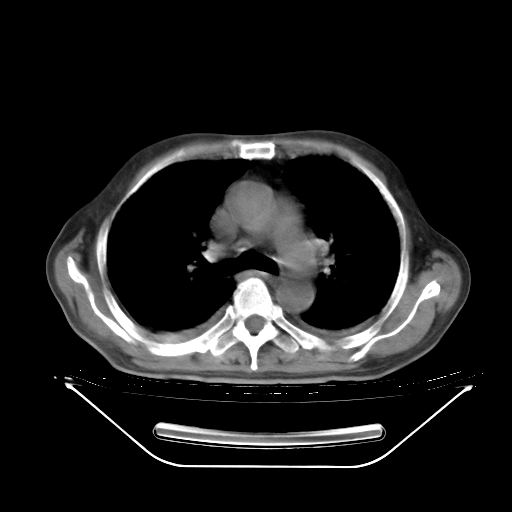

今天复查肺部CT,发现双肺广泛磨玻璃样改变。所以我把3月19日和5月9日相隔50天的肺部CT上传。请大家会诊。

5月9日肺部CT(在4月27日齐鲁医院肺部CT描述部分肺组织磨玻璃样改变,12天后肺组织广泛磨玻璃样改变)

2009年5月9日肺部CT

大致读了系列胸部CT:纵隔窗无明显异常,肺窗:从4、27至今:主要是双肺中下野外带可见毛玻璃样改变,目前处于急性肺泡炎阶段,至于原因考虑1、结替组织或胶原血管性疾病所致?2、恶性疾病如恶组在肺部所致的表现或细支气管肺泡癌?3、药物或其它原因如肺蛋白沉着症所致肺泡炎目前不太可能?总之,明天就去请我院的呼吸科、感染科、血液科和临免专家会诊哈。